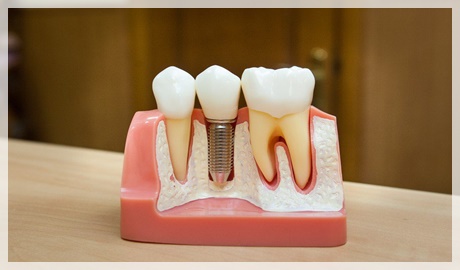

Bunlardan en uygununa karar verildikten sonra çene kemiğine implant yerleştirilir. İmplant tedavisi bir kişinin bir ya da daha fazla dişini kaybettiğinde ve yerine yeni diş yerleştirilmesini istediğinde gerçekleştirilen bir tedavi yöntemidir. Implant diş tedavisi iki aşamadan oluşmaktadır. İmplant tedavisinin süresi yapılacak olan implant sayısına ve hastanın çene kemiğine bağlı olarak yarım saat ile birkaç saat arasında da değişebilir.

İmplant diş tedavisi ne kadar sürer. İlk aşama tedavi aşaması olarak değerlendirilir ikinci aşama ise implantın kemiğe kaynama aşamasıdır. 3 3 i̇mplant tedavisi sonrasında ağız ve diş bakımı nasıl olmalıdır. Ortalama olarak 1 hafta kadar sürmektedir.

İmplant tedavisinin süresi. Bazı markalar daha hızlı iyileşen modeller üretmiştir ve bu süre uygun vakalarda 20 güne kadar inebilmektedir. Konvansiyonel yaklaşımdacerrahisiden sonra alt çenede 8 hafta üst çenede ise 16 hafta kemik ile vidanın kaynaşması için beklenmelidir. Hekim dişe en uygun implantın hangisi olduğuna karar verir.